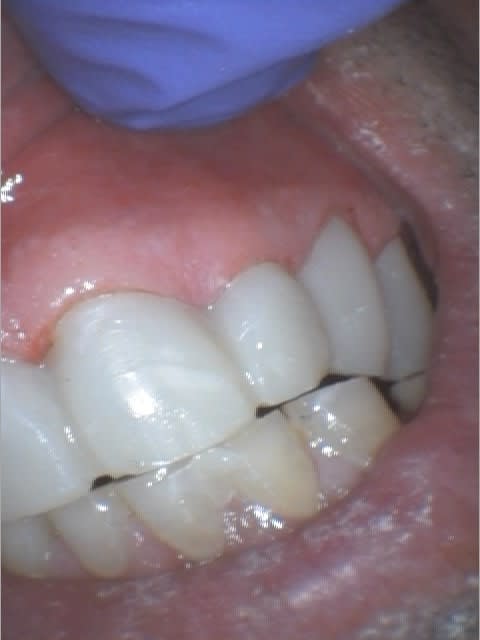

Là en même temps, j'ai remonté ma DVO, et je laisse comme ça quelques jours pour tester...

Le meilleur articulateur c'est la bouche... non? :-)

Quelques remarques :

1 - les dents étaient encore vivante malgré l'importante de l'abrasion. Cela prouve que la pulpe est une bonne obturation, non? J'ai fait les endo du bloc incisivo canin hier, et les provisoires ce matin.

2 - Quand il n'y a plus de calage postérieur, ça le part pas toujours en éventail : théorie du maillon faible... Si le parodonte est faible, ça part en éventail, si les dents sont longues et le parodonte solide + éventuellement occlusion en bout à bout, c'est les dents qui s'usent...